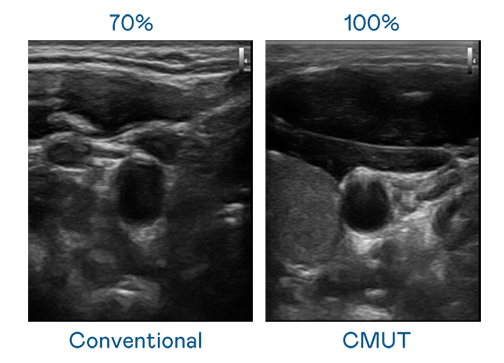

CMUT 技術是一種用電容式微機電元件來產生超音波訊號的技術。與傳統 PZT 壓電式技術相比,CMUT 頻寬增加 30%,更寬頻的超音波訊號讓影像解析度大幅提升,是實現高影像品質醫療超音波掃描、促進精準醫療發展的關鍵技術。

超音波影像的解析度高低,首先取決於探頭能發出的訊號頻寬。AGGAME CMUT 可提供高清晰的超音波訊號,提供高頻寬、高靈敏度、影像紋理細節更高的超音波影像,協助醫護人員縮短影像判讀時間及利用精準的醫療影像進行診斷。